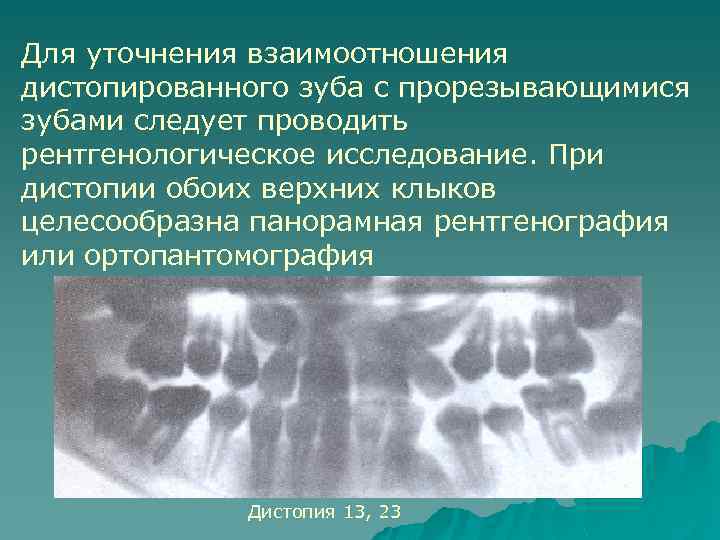

Для уточнения взаимоотношения дистопированного зуба с прорезывающимися зубами следует проводить рентгенологическое исследование. При дистопии обоих верхних клыков целесообразна панорамная рентгенография или ортопантомография Дистопия 13, 23